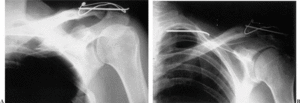

En la radiografía simple del hombro se apreció migración intratorácica de una aguja de Kirschner, procedente de la osteosíntesis realizada en la articulación acromioclavicular izquierda (fig. 1). El paciente fue ingresado para completar el estudio. Durante su ingreso se realizó tomografía computarizada (TC) con contraste para objetivar el grado de afectación de las estructuras intratorácicas, visualizándose una invasión de la cavidad torácica a través del ápex pulmonar izquierdo, sin neumotórax, lesión medular, vascular o mediastínica acompañantes (fig. 2). El paciente fue valorado por el Servicio de Cirugía Torácica del Hospital, y dado que no había afectación de estructuras neurovasculares y que la migración estaba limitada por el arco posterior de una vértebra torácica, se adoptó una actitud conservadora, realizando un seguimiento evolutivo del paciente.

Figura 1. Imágenes radiograficas del caso que se describe: (A) Radiografía anteroposterior del hombro izquierdo, en la que se aprecia la migración de la aguja de Kirschner procedente de la osteosíntesis de la articulación acromioclavicular izquierda. (B) Radiografía anteroposterior del hombro con 30ode inclinación craneal. La aguja se encuentra atravesando el ápex pulmonar izquierdo.